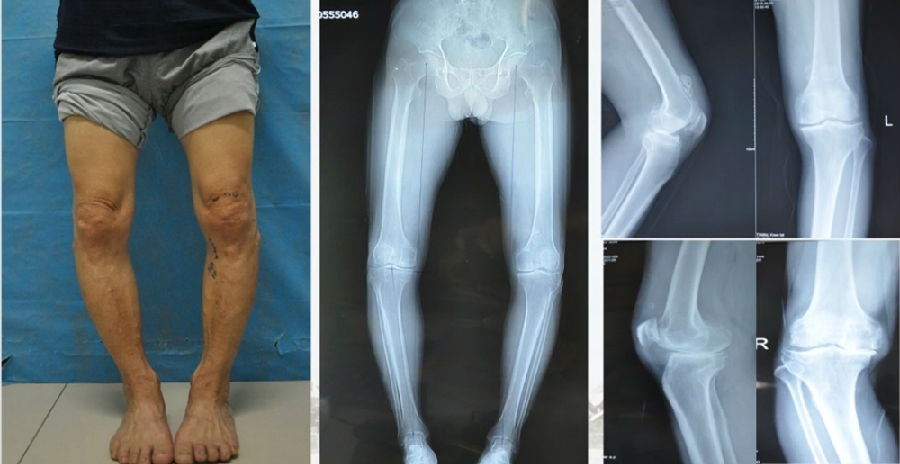

典型病例,男性,65岁,农民,双膝内翻16度。

术前影像

第一次为该患者做了传统上行开放截骨,撑开角度较大,术后用三种方法测量髌骨高度,发现髌骨高度受到影响,髌骨变低了。

左膝上行OWHTO(初次)

上行OWHTO髌骨高度测量

ISI法测量髌骨无明显变化;CDI、BPI法测量髌骨降低明显;患者屈膝锻炼困难。

第二次来院做另一侧肢体时,采用下行截骨,术后患者髌骨高度,无论用哪种方法测量都无明显变化,而且患者膝关节功能迅速得到恢复。

右膝下行OWHTO(再次)

下行OWHTO髌骨高度测量

ISI法测量髌骨无明显变化;CDI、BPI法测量髌骨无明显变化;患者屈膝明显改善。